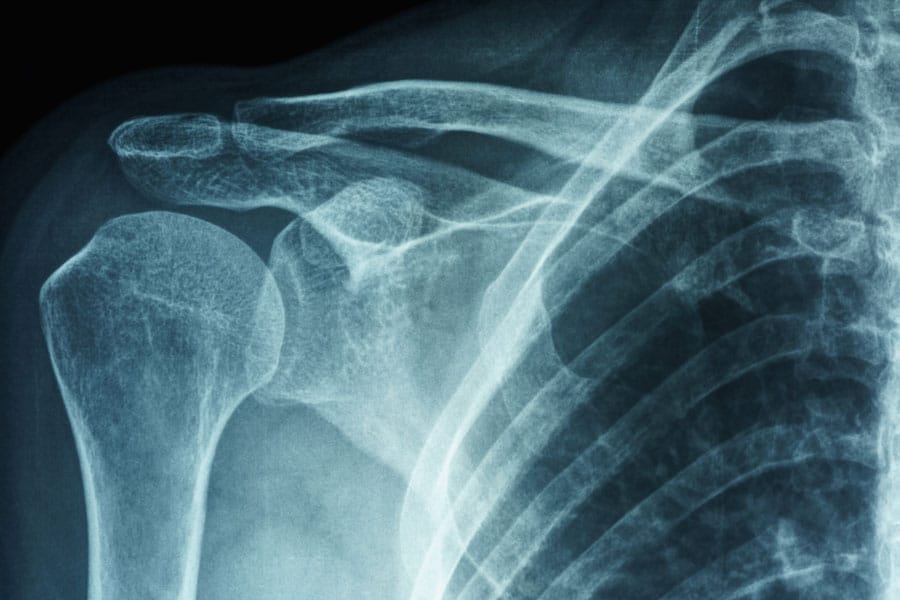

粘连性囊炎(AC),或冻肩,只是一系列影响肩关节的常见疾病之一,其在普通人群中的患病率约为2%。这种疾病表现为肩关节的球窝关节(盂肱关节)僵硬、疼痛和功能障碍。通常伴有周围肌腱套肌肉的问题。交流电在女性和40-60岁人群中最常见。虽然AC通常是自我限制的,可能在一些人两年内解决,它可能导致持续的问题,对许多人,特别是糖尿病患者。

AdCaB研究的第三部分将探讨AC患者的关节手术结果。将在术前、术后3个月和12个月收集患者报告的结果测量。B-CORE和吉隆骨科团队将收集的测量数据包括牛津肩关节评分和牛津肩关节不稳评分。术前和术后的数据将用统计软件进行分析,考虑到年龄和参与者是右撇子还是左撇子等因素,因为这些因素可能会影响结果。